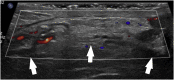

The differential diagnosis of scrotal pain and swelling in adolescent males includes testicular and appendage torsion, epididymitis, epididymo-orchitis, trauma and incarcerated hernia. Physical examination, ultrasound and urinalysis often can identify the etiology of the scrotal pain and swelling. We present a case of left scrotal pain and swelling that was initially concerning for a paratesticular mass. Repeat examination and further imaging during pre-operative assessment was consistent with left-sided vasitis. The diagnosis of vasitis is difficult with ultrasound and commonly requires CT or MRI to differentiate from incarcerated inguinal hernia. Recognition of this uncommonly reported condition may prevent unnecessary surgeries.